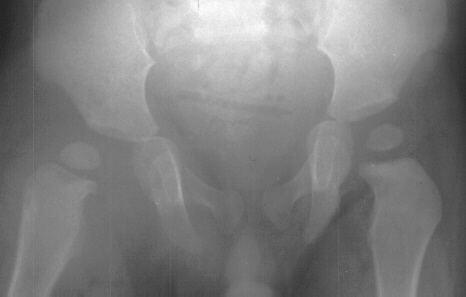

- Post Operative Day 18: R hip Xray: subluxation of R hip, possible metaphyseal

lucency consistent with osteomyelitis. Taken to OR for repeat I & D

Institute. Initial labs: WBC 15,100, ESR 72. R hip Xray: changes in proximal

. metaphysis including lucency and demineralization, hip subluxated. Treated

with oxacillin and Pavlik harness.

- 2 month Office Follow Up: Rt hip Xray: progressive destruction of capital

femoral epiphysis, cystic changes in metaphysis consistent with AVN.